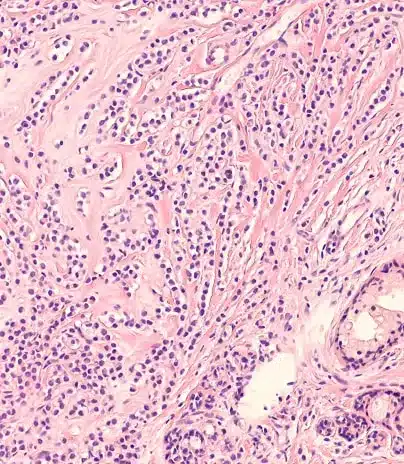

Cáncer de Mama Infiltrante: Una Enfermedad Heterogénea

El cáncer de mama infiltrante, lejos de ser una sola enfermedad, abarca múltiples subtipos con características biológicas y pronósticos distintos. Con los avances en medicina personalizada y farmacogenómica, hoy sabemos que cada tumor es único y requiere un enfoque individualizado.

Hormonas y Receptores

• Entre el 60% de los tumores son receptor de estrógeno (RE) positivos, lo que mejora el pronóstico y la respuesta a la terapia endocrina.